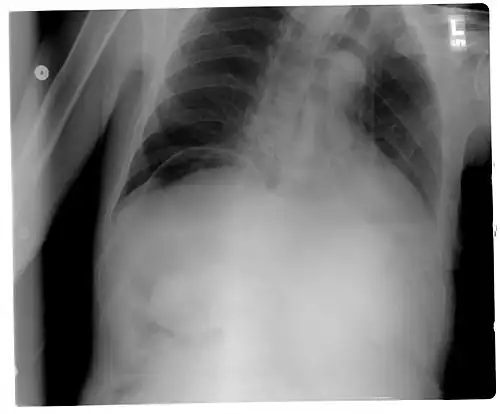

| Frontal chest X-ray. The air bubble below the right hemidiaphragm (on the left of the image) is a pneumoperitoneum. | |

Pneumoperitoneum is pneumatosis (abnormal presence of air or other gas) in the peritoneal cavity, a potential space within the abdominal cavity. The most common cause is a perforated abdominal organ, generally from a perforated peptic ulcer, although any part of the bowel may perforate from a benign ulcer, tumor or abdominal trauma. A perforated appendix rarely causes a pneumoperitoneum.